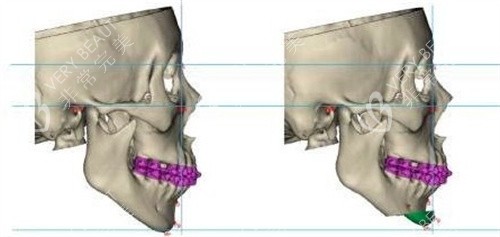

颏成型术:这是一种针对下巴骨骼进行调整的手术。医生会通过切开、移动和固定下巴骨,来改变下巴的位置和形状。它可以从根本上解决下巴后缩等骨头方面的问题,对下巴整体形态的改善较为显著。

颏成型术:适用于下巴后缩情况较为严峻,骨头问题明显的人群。比如先天性下巴发育不良,下巴短小且后缩程度较大,单纯依靠外部填充无法达到理想结果的患者。

颏成型术:由于是对骨头进行调整,术后结果比较持久和稳定,能够从根本上改变下巴的形态,使面部轮廓更加协调自然。但手术改善时间相对较长,可能需要几个月才能完全改善。

颏成型术:因为涉及到骨头的手术,手术风险相对较高,可能会出现出血、感染、神经损伤等并发症。但只要术后护理得当,大多数人都能改善良好。